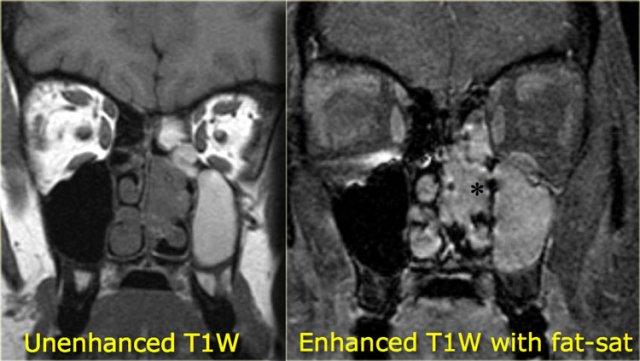

Bên trái là ví dụ về bệnh lý xoang mũi do nhiễm trùng.

Trên ảnh trước tiêm thuốc tương phản từ, thấy nội dung tín hiệu tương đối cao trong các xoang hàm do vật chất giàu protein.

Sau khi tiêm thuốc tương phản từ đường tĩnh mạch, chỉ có hình ảnh ngấm thuốc của niêm mạc xung quanh và không có ngấm thuốc dạng đặc.